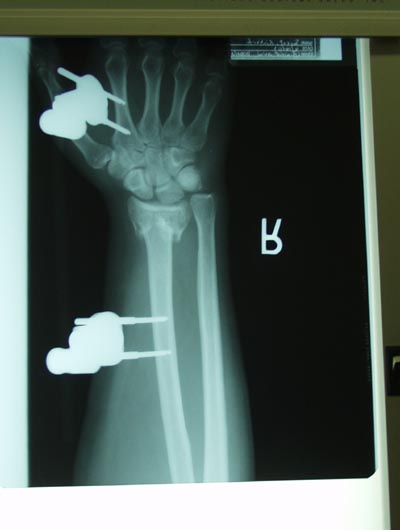

They put an external fixator on my arm to keep the proper alignment for healing. Unfortunatrely, one of the screws came loose and they have to operate again. Several work colleagues had suspected that I had a screw loose for some time. |

| Here is the x-ray. You can see how the pins are screwed into the bone. You can also see how end of the radius is collapsed. |